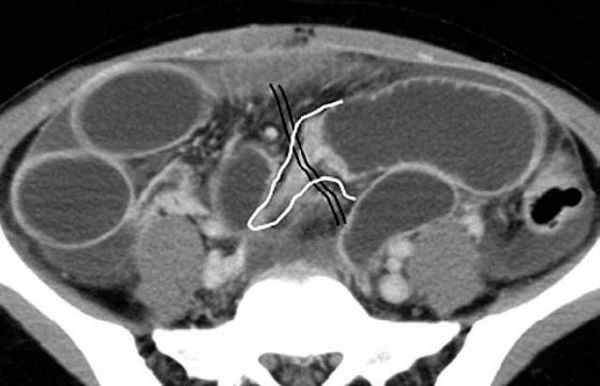

-Расширенные петли тонкой кишки проксимальнее транзиторной зоны (зоны обструкции).

-Под транзиторной зоной надо понимать зонy кишки с очевидной разностью в диаметре просвета между расширенным проксимальным сегментом и местом сужения/обструкции. Визуализация этой зоны зависит от причины и механизма обструкции, а также от проекции расположения петли (аксиально, фронтально и т.д.). К сожалению, обнаружение этой зоны не всегда представляется возможным. При спаечном механизме или воспалении многими хорошо описан признак "птичьего клюва". При обструкции в результате алиментарного болюса транзиторная зона будет выглядеть как гетерогенное образование в просвете кишки без признаков контрастного усиления.

Различные КТ сканы при простой форме обструкции, cxематично изображены транзиторные зоны и спайки, которые как "хомут" или "удавка" как-бы душат петлю кишки.

Значение реконструкций в разных проекциях для определения уровня обструкции.